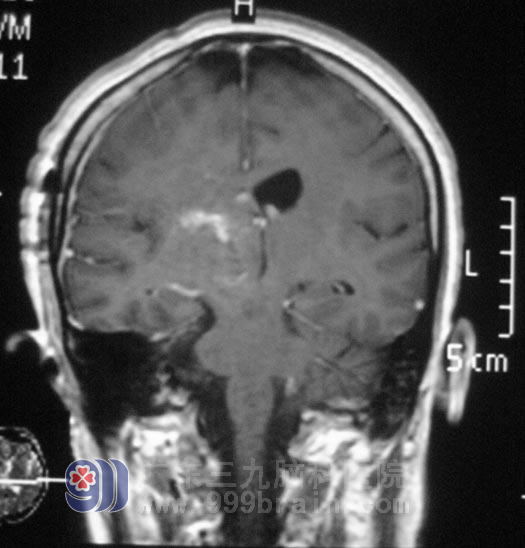

在广东三九脑科医院综合神经外科,通过MR、DSA检查,鲁明主任考虑病变部位为海绵状血管瘤。完善相关检查后,由鲁明主任主刀,在唤醒麻醉下行右侧基底节区、丘脑海绵状血管瘤切除术+血肿清除术,显微镜下切除右侧基底节区、丘脑处海绵状血管瘤及陈旧血肿,对她的语言及肢体运动功能完好保护。治疗后,姚女士术前症状基本消失,行走自如。术后病理结果为:海绵状血管瘤。

▲手术后